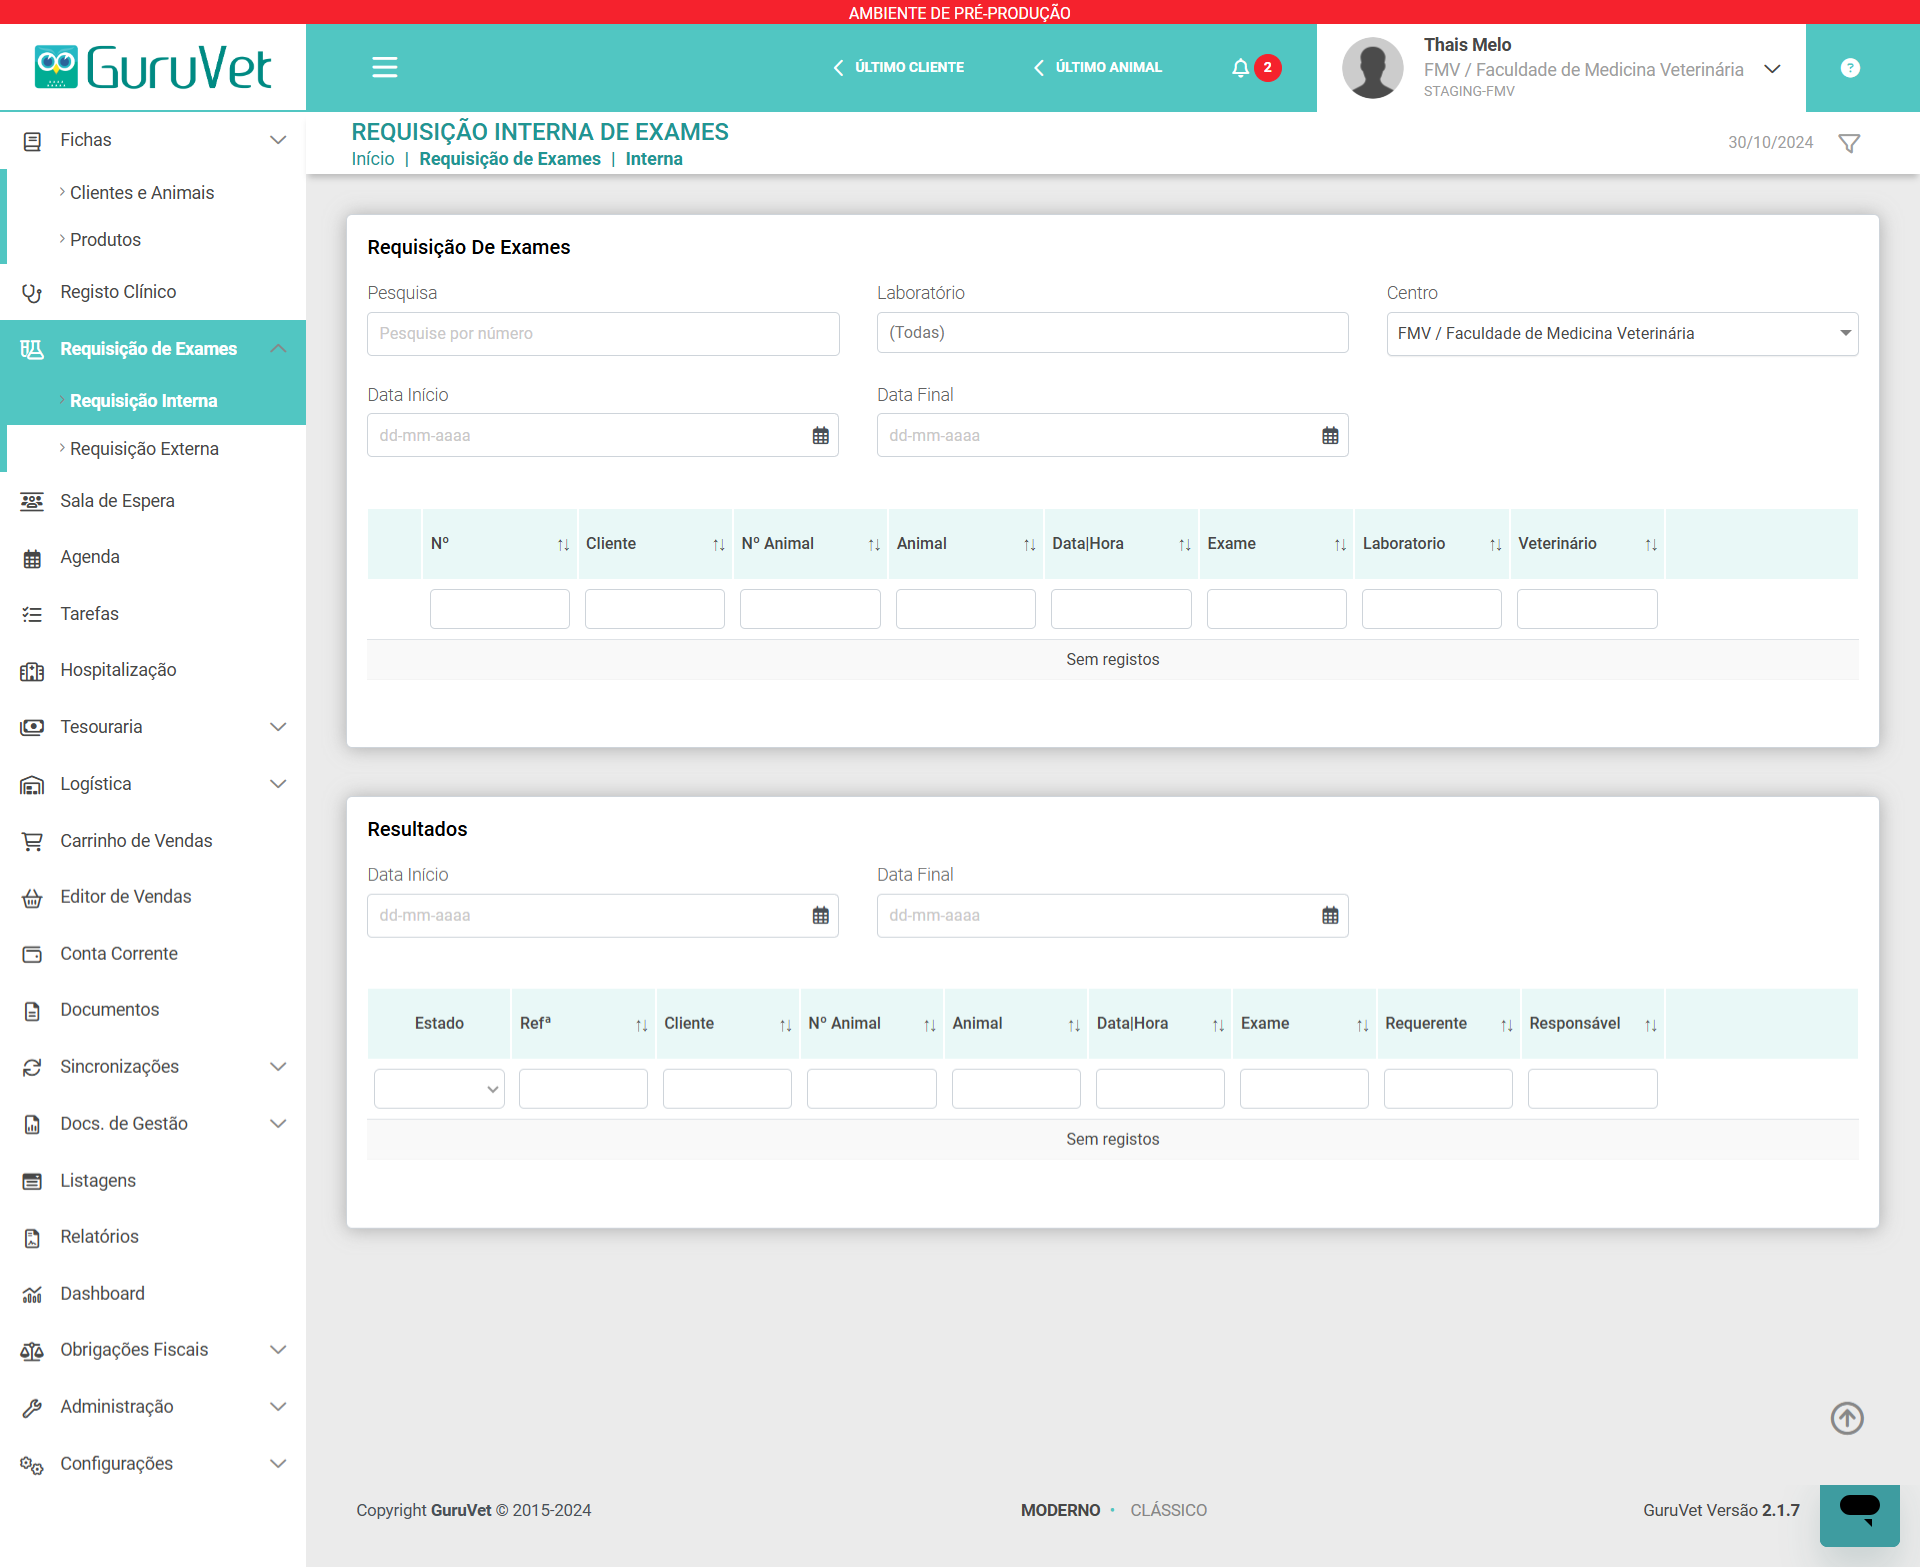

Disponha de todos os recursos necessários para uma gestão eficaz da sua clínica ou centro veterinário, num único software.

Aceda com facilidade ao histórico médico dos pacientes, bem como aos resultados de exames clínicos e de imagem.

PRODUTO

GuruVet - Software de Gestão para Clínicas e Centros Veterinários

O GuruVet é um sistema para clínicas veterinárias desenvolvido para ser o mais completo, intuitivo e fácil de utilizar possível, de forma a apoiar o veterinário e a sua equipa. Para criar o GuruVet, reunimos especialistas de várias áreas (administrativa, jurídica, contabilística, veterinária e tecnológica) para estudar o funcionamento dos centros veterinários e desenhar os processos de acordo com as boas práticas de gestão.